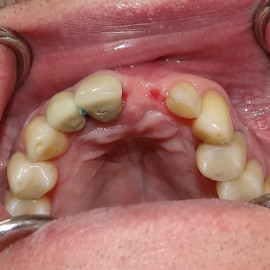

Po utracie zęba w przednim odcinku łuku zębowego należy zwrócić wzmożoną uwagę na aspekt estetyczny. Naczelnym przesłaniem odbudowy brakujących tkanek (anatomiczno-funkcjonalny kompleks tkanek: kość wyrostka zębodołowego + dziąsło + zęby) jest uzyskanie takiego wyniku, który jest najbliżej ideału, czyli takiej sytuacji jak gdyby nic się nie stało i w ogóle nie doszło do utraty zęba i tkanek około zębowych. Kluczem do sukcesu jest odtworzenie poprawnych stosunków anatomicznych: kość - dziąsło - ząb.

Korona protetyczna na implancie, funkcjonująca od roku 2003. Zdarzył się wypadek motocyklowy. Widzimy klucz do osiągnięcia sukcesu: mikrochirurgia i poprawna anatomiczna odbudowa tkanek. Tego nie zastąpi nawet najdroższy implant!

Pokazano etapową odbudowę brakujących tkanek, wraz z odbudową objętości i kształtu dziąsła.